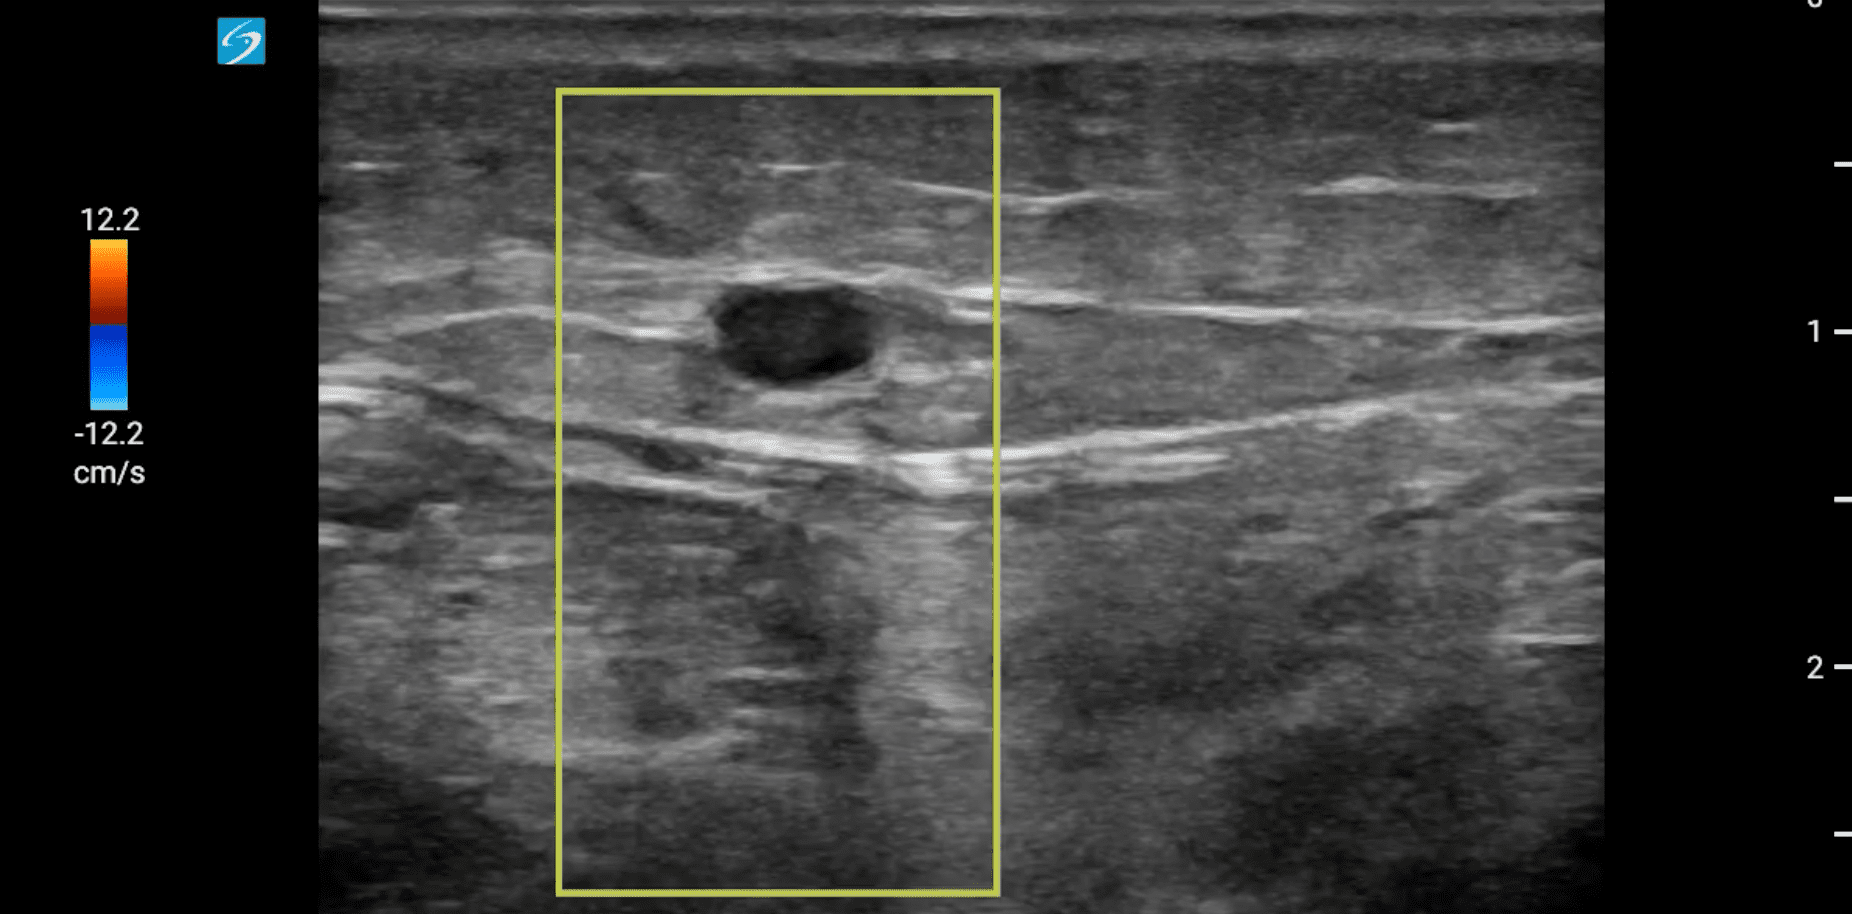

Hallazgos ecográficos

Se localiza ecográficamente la vena femoral común con una imagen hipoecogénica que no colapsa con a la compresión y que se extiende por femoral superficial hasta poplítea. Tras hallazgos, se realiza también una ecografía cardíaca, con un diámetro de visu VD/VI < 1 y con una función cardíaca conservada, con resultado en escala PESI de riesgo bajo.

Como diagnóstico diferencial se valoran celulitis e insuficiencia venosa crónica. Se realiza una ecografía reglada que confirma el diagnóstico de sospecha de trombosis venosa profunda (TVP) extensa subaguda.